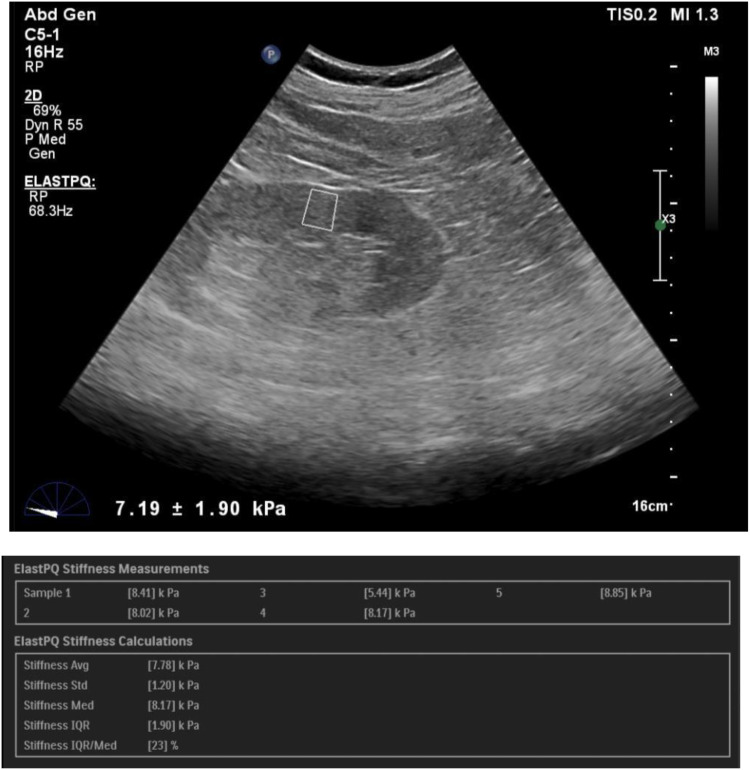

Materials and methods: The study protocol was approved by the Institutional ethics Committee at Kasturba medical college, Manipal and written informed consent was obtained from all participants. The study included 93 control subjects and 108 patients with CKD. SWE imaging was performed to assess renal cortical stiffness, as measured by the Young's modulus (YM). Correlations between SWE and conventional ultrasound parameters with age, serum creatinine, eGFR and serum urea were analysed using Pearson's correlation coefficient (p ≤ 0.05) and receiver operating characteristic (ROC) curves were derived.

Results: The diagnostic performance of SWE correlated with serum creatinine levels and eGFR. We found a statistically significant difference in kidney stiffness values between healthy individuals and CKD patients. The Spearman correlation coefficient revealed moderate negative linear correlation between the YM measurements and eGFR. We obtained a YM measurement cut-off value of 4.43 kPa, a value less than or equal to this suggested a no diseased kidney. This yielded sensitivity and specificity of 92.6% and 80.6%, respectively, with an AUROC of 0.92.